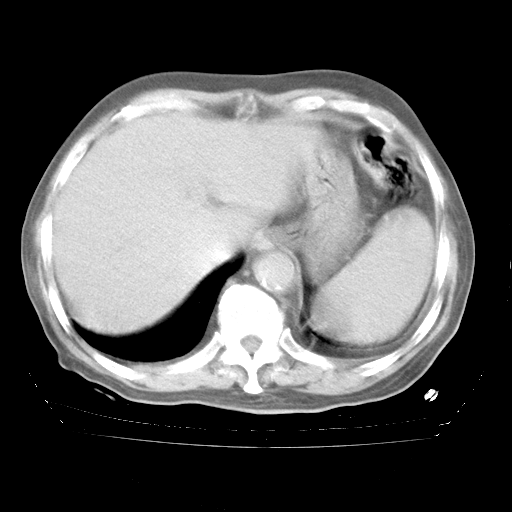

4月28日肺部CT

个人阅读4.14日肺部CT平扫:纵隔窗无异常,但肺窗示:双下肺内、后基底段有片絮状侵润影,部位以后基底段为著,以间质改变为主,呈急性肺泡炎征像,和首次住院影像学有相似之处。仅是个人读片,明日请相关专家再读片哈。其它建议同上。

1、108#的是4月14日的胸部CT(发此贴时还没看着28日的CT)。14日的胸部CT其实已经出现改变(如108#所述),个人认为28日的胸部CT除纵膈窗疑似有双侧胸膜增厚或少量胸积液(可行胸部B超明确)外,与4月14日对照病变有所加重;2、已经给予“异烟肼、利福平、乙胺丁醇”抗痨治疗?如果是,甲强龙80mg可缓慢减量;如果环磷酰胺已停用,暂不使用;3、中性粒细胞92%,明显升高,目前体温情况?注意合并细菌感染可能,使用左氧氟沙星情况下,是否联用B-内酰胺类抗菌药物?另外是查免疫全套非风湿全套。